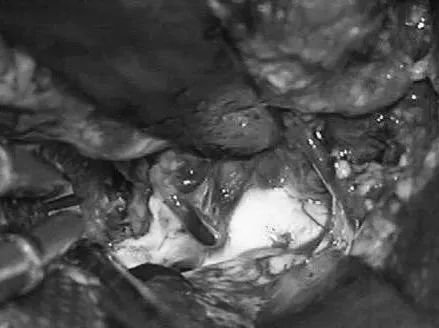

Lawton教授术中操作

通过ITG经皮层显露可以充分显露颞角,达到全切AVM。

- 第7步:将AVM移出脉络裂,以切断lPChA供血,辨认环池内的BVR。